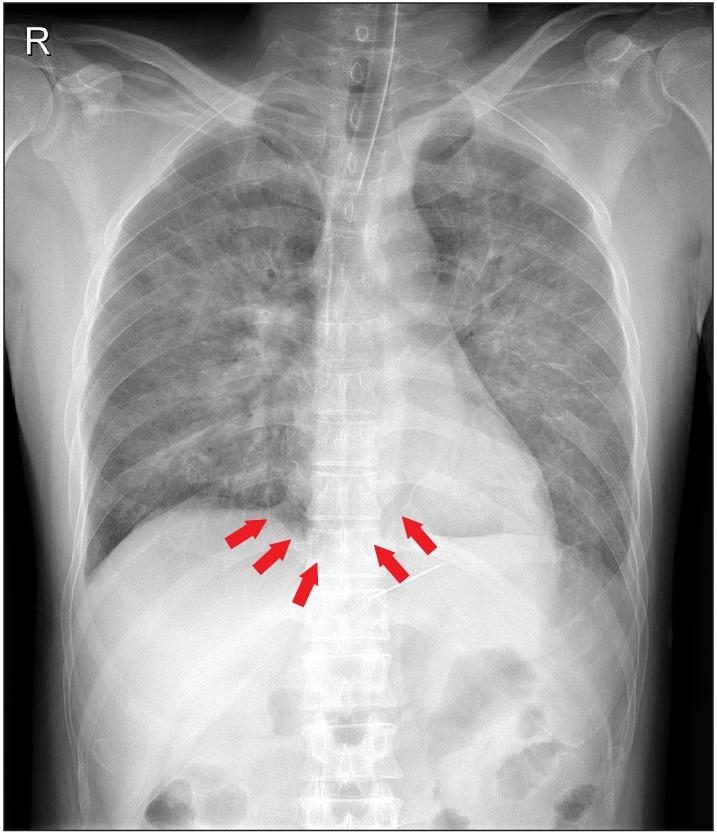

Recurrence of fatal venous air embolism.